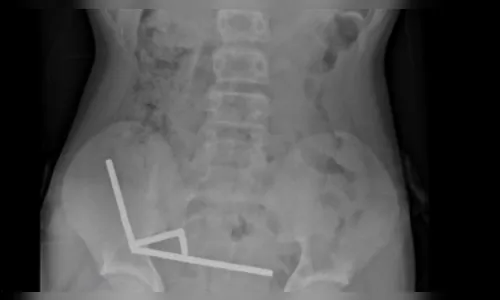

Exames de imagem mostraram que os ímãs haviam se agrupado em quatro correntes na parte inferior direita do abdômen, conectando diferentes regiões do intestino pela força magnética. Essa ligação causou necrose por pressão — morte do tecido intestinal devido à compressão —, além de risco de perfuração e infecção severa.

Durante a cirurgia exploratória, os médicos conseguiram remover todos os ímãs, mas precisaram retirar partes do intestino delgado e grosso danificadas. O adolescente se recupera bem.